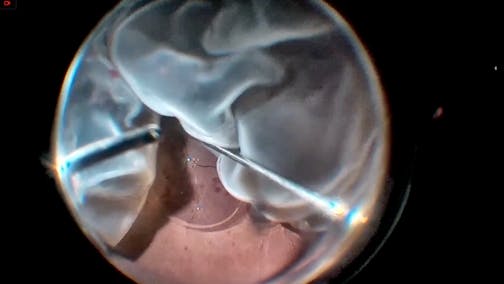

Induction of PVD

Fabio Patelli, MD